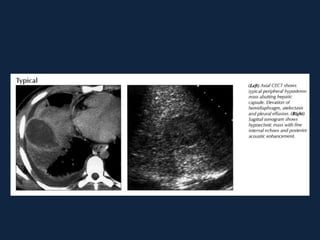

Abscessos Piogênicos

► Coleção localizada de pus no parênquima       hepático

devido a uma infecção bacteriana.

► Origem:

 Infecções intestinais com disseminação hematogênica

secundária (diverticulite)

 Infecções de vias biliares (colangite)

 Extensão direta (vesícula biliar , rim direito...)

 Gram negativos e anaeróbios

► QC: paciente de meia idade a idoso com febre,

desconforto abdominal, hepatomegalia, leucocitose

► Icterícia (40%)

►s/c: Lesão grosseiramente arredondada, hipodensa

(0-45 HU), podendo conter septações e gás (sinal

específico, presente em menos de 20% dos casos).

Pode haver nível ar-fluido e fluido-debris.

►Realce anelar e/ou das        septações   após   a

administração do contraste.

►Pode haver derrame pleural e atelectasia de lobo

inferior direito.